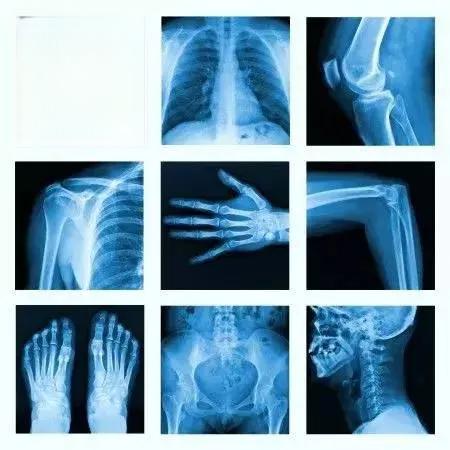

骨科检查中常用的影像学检查方法主要有三种:X光、CT和MRI。这三种方法各有特点,适用于不同的骨科疾病诊断。

X光是最常用的骨科检查方法之一。它的原理是利用X射线穿透人体,不同组织对X射线的吸收程度不同,从而在底片上形成黑白对比的影像。X光检查简单快速,价格低廉,特别适合观察骨骼的整体情况。例如,X光可以清晰显示骨折、关节炎、骨质疏松等病变。然而,X光也有局限性,它无法清晰显示软组织结构,且深浅组织的影像会相互重叠。

CT(计算机断层扫描)是X光检查的升级版。它通过从多个角度拍摄X光片,然后利用计算机重建出三维图像。CT可以提供更详细的骨骼结构信息,特别适合观察骨折的细节、骨肿瘤的形态等。CT的缺点是辐射剂量较高,且价格比X光检查更贵。

MRI(磁共振成像)是目前最先进的医学影像技术之一。它利用强磁场和射频脉冲来产生人体内部结构的详细图像。MRI特别擅长显示软组织结构,如肌肉、韧带、软骨等。因此,对于椎间盘突出、肩袖损伤、膝关节韧带损伤等疾病,MRI是首选的检查方法。MRI的优点是无辐射,但缺点是检查时间较长,费用较高。